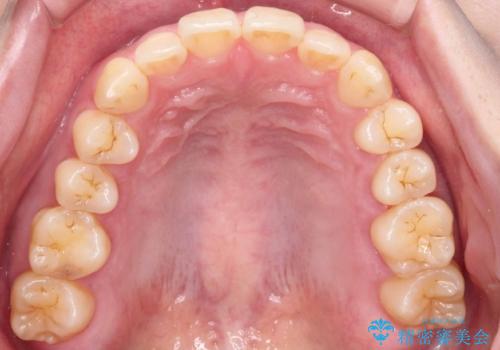

- 「下の前歯が斜めになっている」を主訴に来院された患者様です。

下顎前歯に叢生があり、右上2は反対咬合の状態でした。

昔から食いしばりがあるのを患者様が自覚されており、そのせいか口が開けにくいことも悩まれていました。

下顎前歯の叢生がとれ右上2の反対咬合も改善し患者様にも満足していただけました。治療期間は1年~1年半を見込んでいましたが、患者様の協力もあり10か月で矯正を終えることが出来ました。

インビザラインの性質上、食いしばりや歯ぎしりがある方は咬み合わせが甘くなることがあります。そのような時は保定装置にベックタイプのリテーナーを組み合わせることで改善できます。